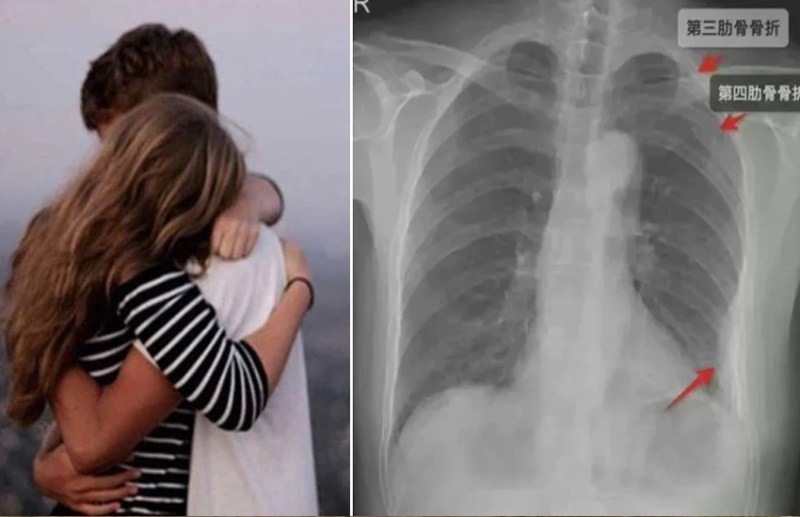

दरअसल, चीन में एक शख्स ने अपने साथ काम करने वाली लड़की को इतना जोर से गले लगाया कि उसकी सीने की पसलियां ही टूट गई है। इसके बाद महिला ने अपने सहकर्मी पर मुकदमा दायर किया। कथित तौर पर उसके सहकर्मी ने बहुत कसकर गले लगा लिया। जिससे उसकी सीने की तीन पसलियां टूट गईं। सहकर्मी को महिला यूंक्सी कोर्ट तक ले गई और कथित पसली तोड़ गले लगाने के कारण इलाज में लगे पैसों के लिए मुआवजे की मांग की।

एक्स-रे में हुआ खुलासा

महिला ने बताया कि उसे इतनी जोर से गले लगाता है कि चीख निकल गई। इस घटना के बाद उसे सीने में अजीब सा दर्द महसूस हुआ। उसने गर्म तेल की मालिश की और सोने चली गई। पांच दिन बाद महिला के सीने में अचानक दर्द उठा और फिर वह अस्पताल चली गई। एक्स-रे करवाया तो पता चला कि तीन पसलियां टूट गई थीं। महिला ने अपने टूटी हुई हड्डियों का इलाज करवाया।